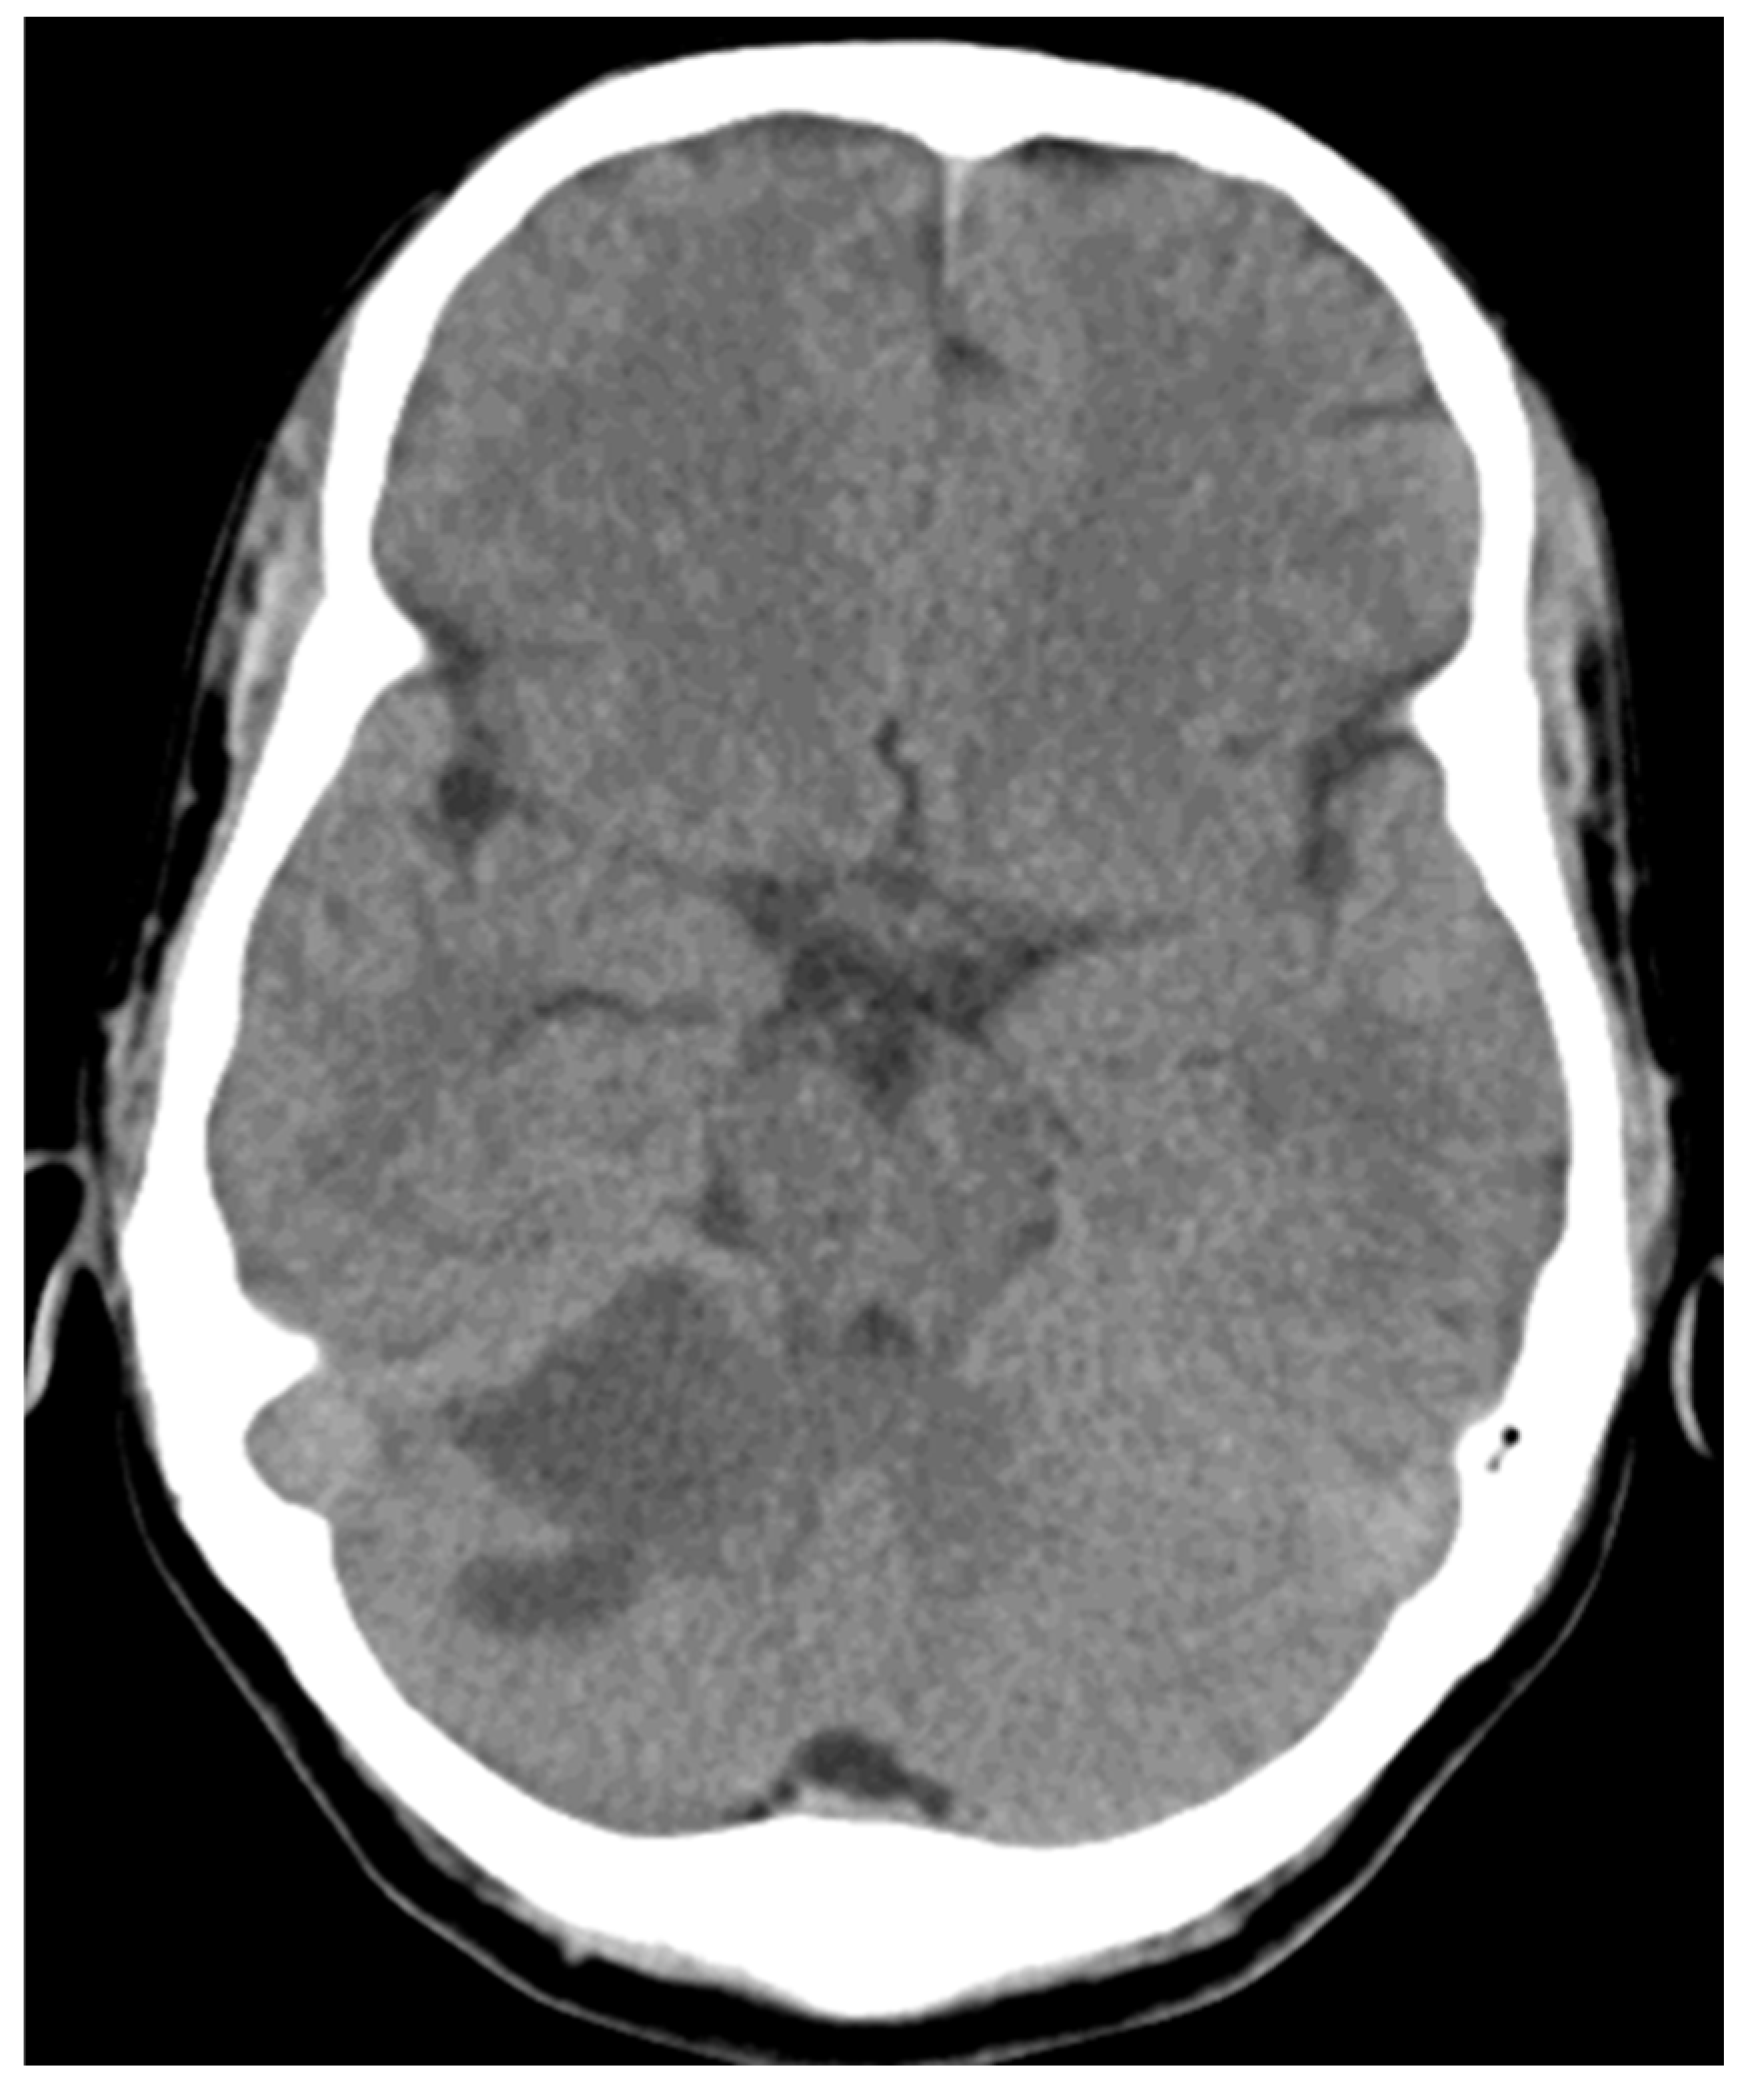

Case 1: A 61-year-old man with complaints of left-sided hemiplegia for 4 hours.

He was presented to the clinic with a loss of consciousness. The CT scan shows a large hypodensity involving the entire right temporal lobe, extending superiorly to the right parietal lobe.

ASPECTS MCA- 6, ASPECTS PCA- 10

The patient was admitted to the ICU, intubated for 2 weeks with no improvement and expired on day 17 of admission.

Figure 1. NCCT of case 1.